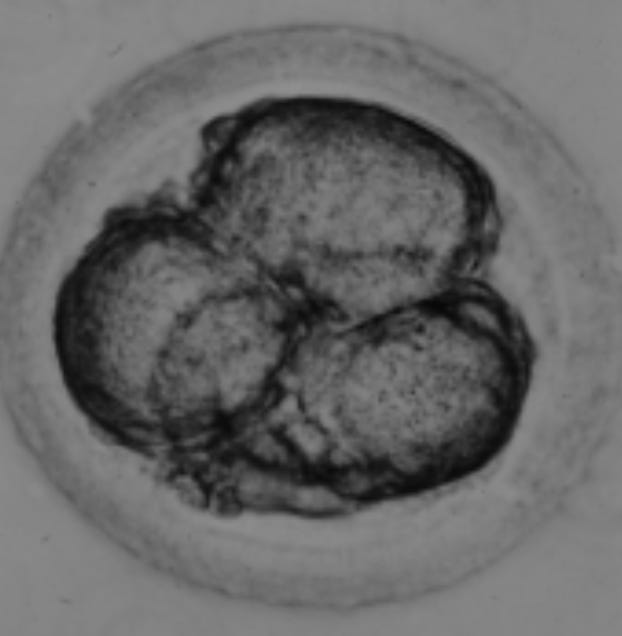

Figure 2. shows a 4-cell human embryo where the blastomeres have separated into equal sized cells that will eventually follow a path to becoming the inner cell mass and embryo proper OR will become positioned towards the outside of the embryo and will pursue a line of development leading to the placenta-the so-called trophectoderm. Note this image is taken from Carnegie Collection and represents likely the first ever human embryo seen and studied at this stage of development.